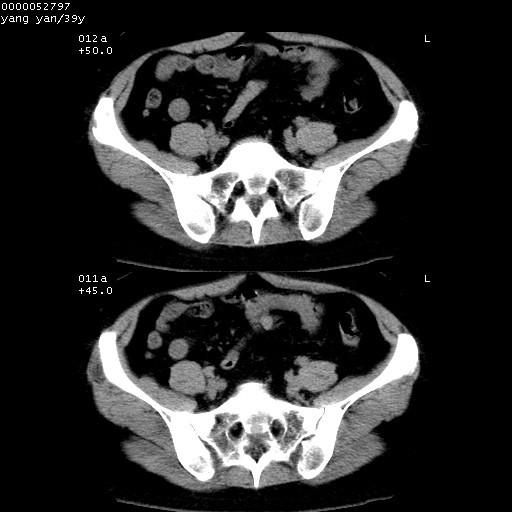

患者 女,39岁。因外伤检查,偶然发现。

典型!双侧骶髂关节致密性骨炎。

典型!病变主要累及双侧髂骨。常见于育龄期妇女。

致密性骨炎,一般不跨越关节面,可是这个骶骨关节面也有硬化。

髂骨致密性骨炎系一种以骨质硬化为特点的非特异性炎症,有高度致密的骨硬化现象,尤其以髂骨下2/3更为明显,但关节间隙则无改变。因位于骶髂关节,且该关节症状明显,故又称之为“骶髂关节致密性骨炎”。 本病90%以上为中年女性,以妊娠后期、尤其分娩后为多见,亦可见于尿路或女性附件慢性感染后,或盆腔内其他感染。此外,臀骶部的外伤亦可诱发或引起本病。  妊娠、分娩及外伤均可引起骶髂关节韧带的撕裂而易使局部的血供受阻。因此早期局部呈现充血、水肿及渗出增加等,渐而局部出现增生与变性反应,随着胶原纤维的致密化而向硬化演变;血管形成厚壁血管,易闭塞而引起髂骨耳状面处缺血和缺氧,骨质呈现硬化性改变,以致手术时局部出血较少。骶髂关节囊壁显示纤维增生、弹性降低及松动样改变。继发于盆腔内炎症者亦出现相类似的病理改变,可能系细菌内毒素作用所致。